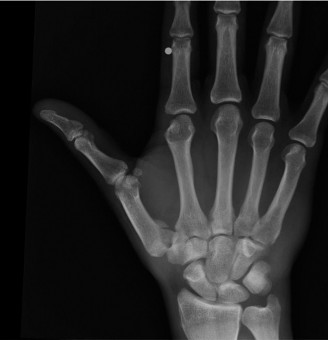

Standard posteroanterior (PA) and lateral radiographs of the wrist often fail to adequately visualize the pisotriquetral joint due to bony overlap from the distal pole of the scaphoid, the capitate, and the triquetrum itself. To properly assess this articulation, a 30-degree supinated AP view (the pisotriquetral view) is mandatory. In our first patient (referencing the classic Figure 3-10), this specific view reveals profound joint space narrowing, subchondral sclerosis, and prominent osteophyte formation at the pisotriquetral interface.

It is crucial to understand the osteology here. The pisiform is an atavistic, sesamoid bone. It is the only carpal bone that does not participate in the complex intercarpal kinematics of the proximal or distal rows. Instead, it lies entirely within the tendon of the flexor carpi ulnaris (FCU). The FCU-pisiform complex extends distally via robust ligamentous attachments: the pisotriquetral ligament, the pisohamate ligament, and the piso-5th metacarpal ligament. Notably, there is no piso-scaphoid ligament; the scaphoid resides on the entirely opposite side of the carpus.